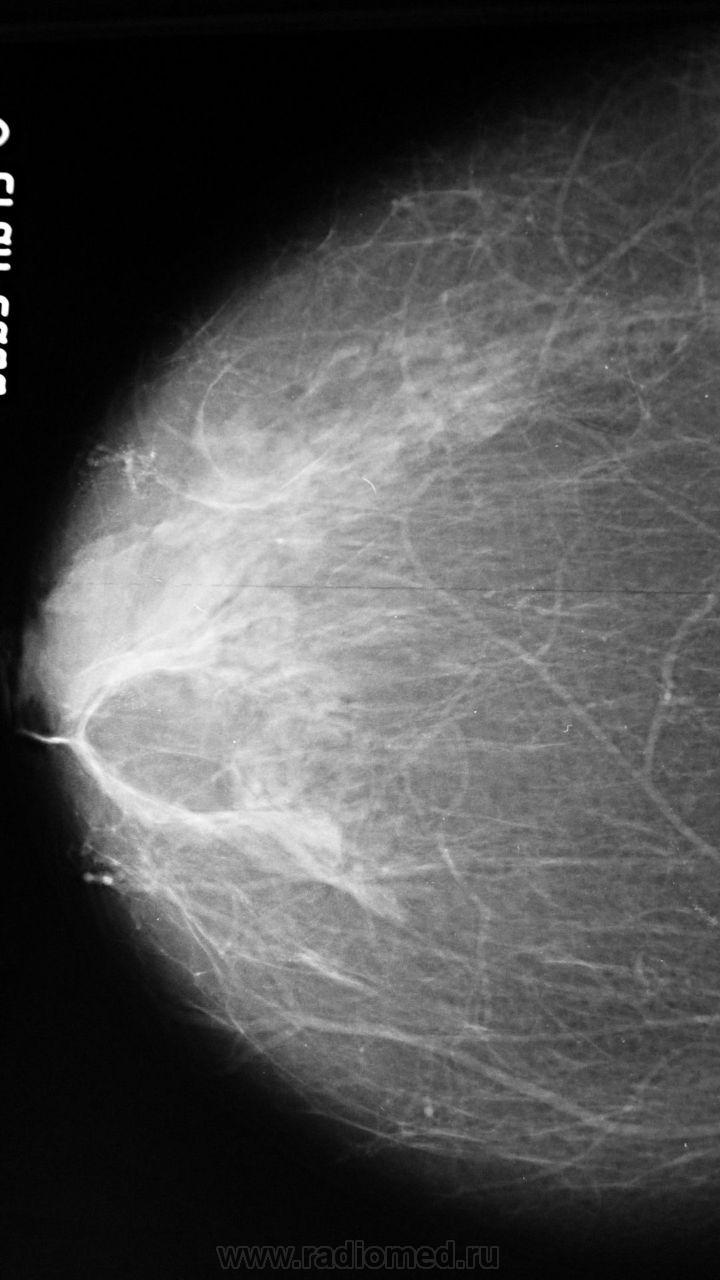

Ваше мнение о левой железе..?

образование жировой плотности - липома или жиросодержащая киста

Липома, с толстой фиброзной капсулой, должна пальпироваться. Для жиросодержащей кисты вроде как великовато.